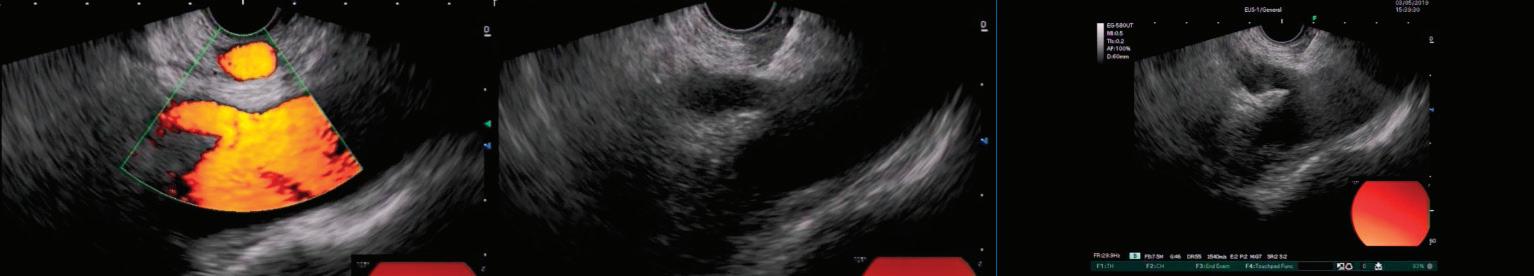

П. Карагьозов, д.м., FASGE Отделение по Интер венционална Гастроен терология "Аджибадем Сити Кли ник УМБАЛ Токуда"София НЕВРОЛИЗА НА ПЛЕКСУС ЦЕЛИАКУС (EUS-CPN) Процедурата е докладвана за пръв път през 1996 г. от Wiersema et al.[1] Aвторите представят опита си с 30 пациенти с напреднали онкологич ни заболявания (25 с панкреасен кар цином и 5 с интраабдоминални ме тастази). Всички са били със силна коремна болка, налагаща прием на опиоидни аналгетици. С помощта на радиален ехоендоскоп и прототип на игла, при всички трансгастрално в плексус целиакус е инжектиран бу пивакаин и 98% дехидратиран абсо лютен алкохол. Използван е т.нар. „билатерален достъп“, при който се инжектира от двете страни на ко ремната аорта. Наблюдавана е сиг нификантна редукция в скоровете за болка. За среден период на про следяване

прилага амбулаторно и в същата сесия, заедно със стадиращото из следване[1]. Впоследствие става ясно, че липсват значими разлики в тех ническия и клиничен успех между EUS-CPN с централен и билатерален достъп и във връзка с по-малкото не желани реакции, централният дос тъп е за предпочитане[2] (Фиг. 1).

10 седмици 88% от паци ентите са имали трайно подобре ние. Нежеланите реакции са били минимални. Само при 4 случая е наблюдавана бързопреходна диа рия. EUS-CPN е ефективна и безопас на процедура и подобрява контрола на болката при интраабдоминал

като приложение то им за дренаж на псевдокисти остава спорно, предимства та им при WON са до казани. Според меж дународен консенсус LAMS са най-подхо дящите стентове за дренаж на WON с ре дица преимущества пред пластмасови те стентове[8]. Спо ред данни от големи проучвания, LAMS са с доказани пре димства пред пласт масовите стентове при дренаж на WON, докато при псевдо кисти трябва да се имат предвид спе цифичните усложне ния, свързани с при ложението им[9] (Фиг. 3-5).

Фиг. 3

Трансгастрална позиция на LAMS при дренаж на некротична колекця- ен досонографски

и ендос копски аспект Фиг. 2 Стент със специален ди зайн Hot AXIOS (Boston Scientific Corp.) Фиг. 4 Ендоскопски аспект на некротичната колекция Фиг. 5 Компютърна томогра фия, демонстрираща пълно обратно развитие на некротична колекция след поставяне на транс гастрален стент ради което рискът от ликидж, билиарен перитонит или раз витие на други фа тални компликации е значимо по-висок.